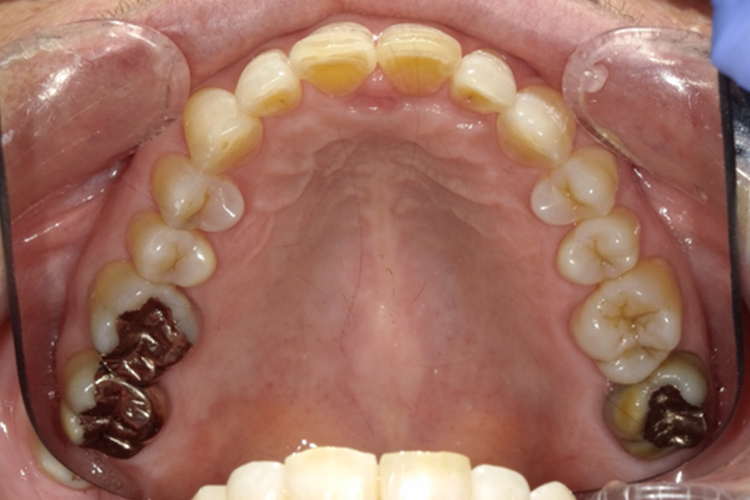

治療前

治療後